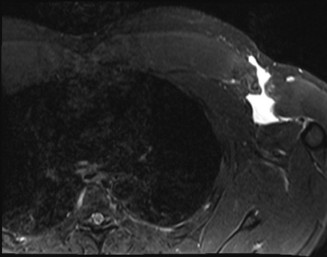

CT arthrograms of the patient’s left shoulder are shown in Figure 2–56. CRP is <3, ESR 45. The patient continues to have pain, so you decide to perform arthroscopic biopsy to obtain tissue cultures. Frozen sections show <5 PMNs per hpf, and Gram stains are all negative.

Figure 2–56

The correct answer is (B). Figure shows contrast under the glenoid component. Given the patient’s normal inflammatory markers and frozen sections combined with continued pain and loosening on CT, infection with P. acnes(an organism that is very difficult to isolate) should be investigated by holding any cultures for at least 2 weeks to see if it will eventually grow. Chocolate agar (Choice C) is mainly used for growing species such as H. influenzae and Neisseria meningitidis not P. acnes. A is incorrect since the patient’s cell count and frozen sections are clearly abnormal, therefore referral to pain clinic would not be appropriate. However, Choice D would be too aggressive an approach given that no organisms have been isolated, frozen sections show <5 PMNs per hpf, and the patient has relatively normal inflammatory markers.